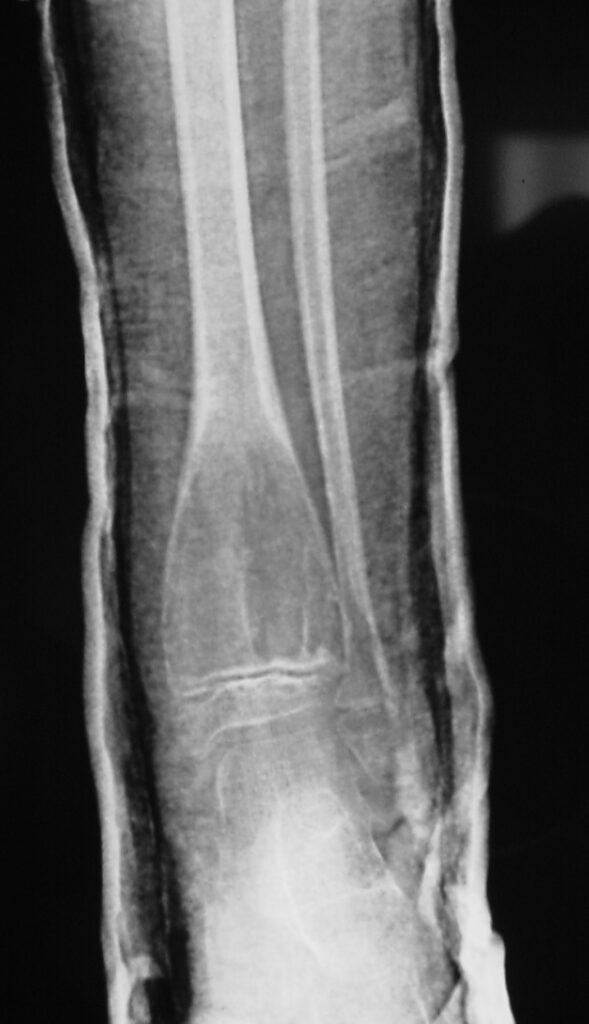

Fig 1a. Plain X-ray (AP View). ABC of the Distal Tibia: Geographic Well Circumscribed Lesion in the distal tibia. The cortices are expanded. There are internal septations. There is no internal mineralization. There is no evidence of a malignant appearing periosteal reaction such as a sunburst or hair on end pattern or codman’s triangle.